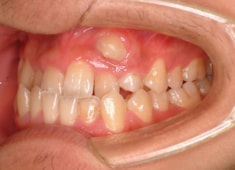

反対咬合+左上3番高位埋伏

(受け口+左上3番目の永久歯が上顎の中に埋まったままはえてきていない)

解説:残存している左上乳犬歯Cを抜歯し、そのスペースに左上3番を誘導しました。Cと犬歯ではスペースが足りないので、前歯をアドバンスさせ、反対咬合を同時に解消しております。

治療前